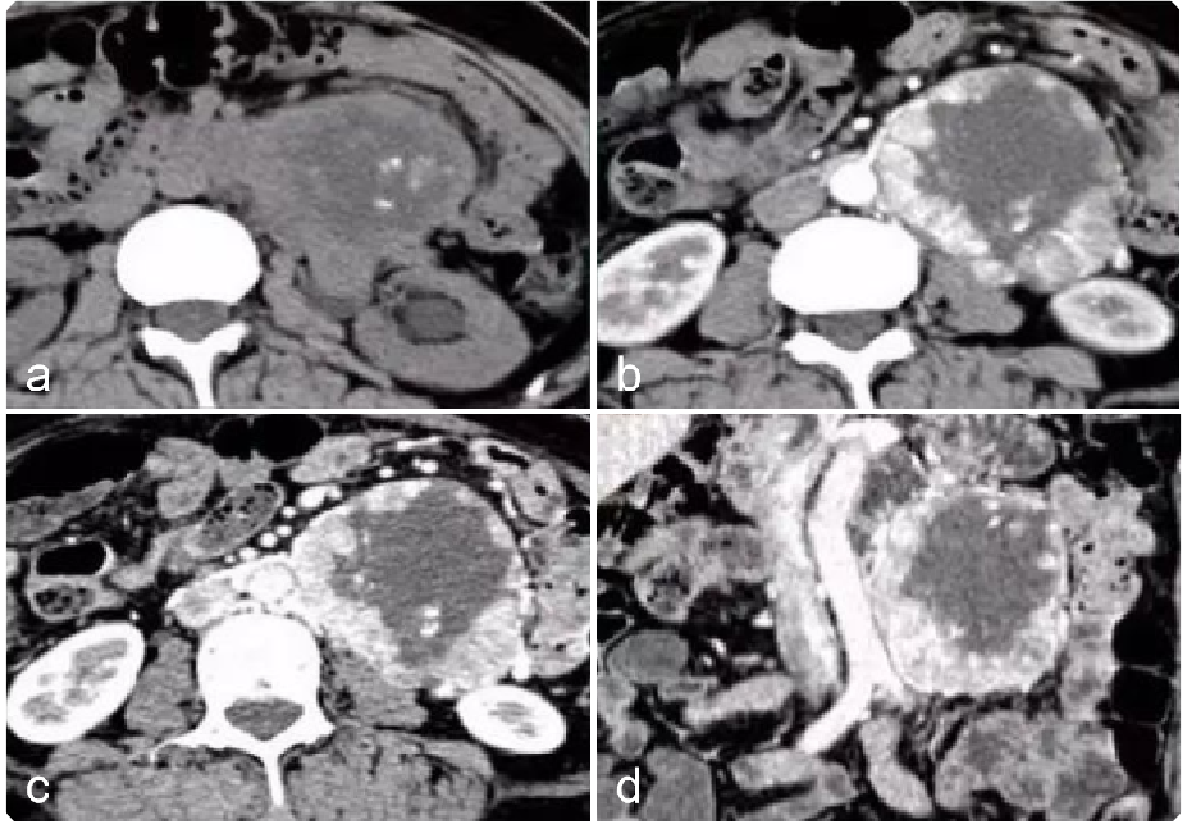

309da72b651fad69b53c1ea5f4ca297c.png 病例 24:(腹膜后)神经鞘瘤囊变  41岁女性,偶然发现腹部肿块(a) CT增强显示低密度肿块,内见线样钙化(箭)。(b) T2WI-FS显示肿块呈不均匀高信号,内见囊变区形成(*)。(c) 大体病理显示肿瘤界限清楚,具有棕黄色实性和囊性切面(箭),其中60%为白色纤维组织,40%为黄色脂肪组织。中央为出血性囊性成分(*)。(d) 镜下显示中央囊肿(*)及周围更小的囊肿(箭)(HE×40)。(e) 高倍镜显示由栅栏样细胞(箭头)组成的Verocay小体,这些细胞被低细胞透明化区域(*)隔开(HE×200)。